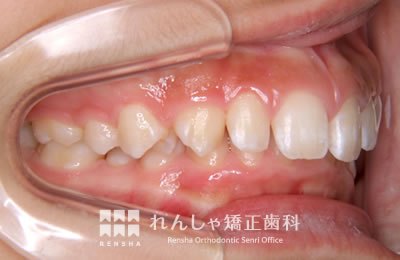

中高生

永久歯列はほぼ完成してしますが、歯列を側方だけでなく後方へも拡大し、埋まっていた右上奥歯を引っ張り出しています。

治療中

→

治療後

| 主訴 | 埋まったままでてこない歯がある |

|---|---|

| 診断名 | Angle Class II 小臼歯の埋伏と叢生を伴う上顎前突 |

| 初診時年齢 | 13歳5か月 |

| 装置名 | マルチブラケット装置 |

| 抜歯非抜歯 | 非抜歯 |

| 治療期間 | 2年3か月 |

| 費用の目安 | 約82万円+消費税(検査料金、都度の処置費用等も合わせた総額) |

| リスク副作用 | 歯の移動に伴う軽微な歯根吸収、歯槽骨吸収、歯肉退縮(本症例では軽度の歯根吸収を認めた)、矯正器具装着中のカリエスリスク増大(本症例ではカリエス発生無し) |